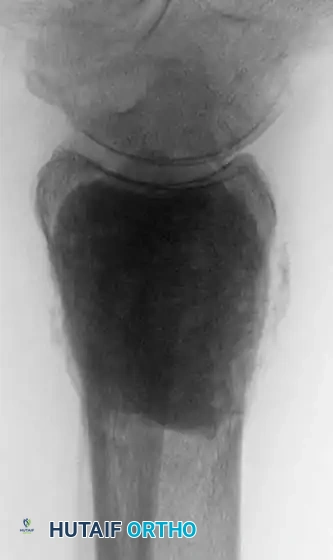

Fig. 22-24: (A, B) Anteroposterior and lateral radiographs of the proximal femur in an 82-year-old man with metastatic kidney cancer revealing multiple lytic lesions. Prophylactic fixation was canceled due to medical instability. (C) Radiograph several weeks later showing a completed pathological fracture. Surgery is now exponentially more difficult, and the patient has suffered severe morbidity.